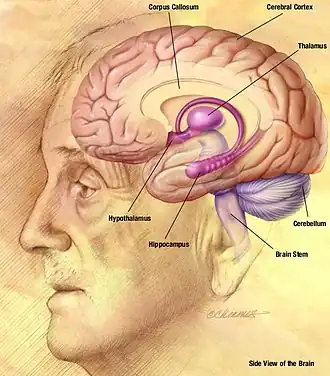

Psychology

The human brain, the focal point of the central nervous system in humans, controls the peripheral nervous system. In addition to controlling "lower", involuntary, or primarily autonomic activities such as respiration and digestion, it is also the locus of "higher" order functioning such as thought, reasoning, and abstraction.[288] These cognitive processes constitute the mind, and, along with their behavioral consequences, are studied in the field of psychology.

Humans have a larger and more developed prefrontal cortex than other primates, the region of the brain associated with higher cognition.[289][290] This has led humans to proclaim themselves to be more intelligent than any other known species.[291] Objectively defining intelligence is difficult, with other animals adapting senses and excelling in areas that humans are unable to.[292]

During sleep humans dream, where they experience sensory images and sounds. Dreaming is stimulated by the pons and mostly occurs during the REM phase of sleep.[301] The length of a dream can vary, from a few seconds up to 30 minutes.[302] Humans have three to five dreams per night, and some may have up to seven.[303] Dreamers are more likely to remember the dream if awakened during the REM phase. The events in dreams are generally outside the control of the dreamer, with the exception of lucid dreaming, where the dreamer is self-aware.[304] Dreams can at times make a creative thought occur or give a sense of inspiration.[305]